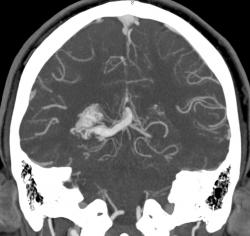

Предсталяю артериовенозную аневризму. Может кому-нибудь будет интересно.

Виден клубок неправильно развитых сосудов, питающихся от задней мозговой артерии и дренирующийся в прямой синус. Перифокальных изменений нет.

Черная стрелка - питащий сосуд - задняя мозговая артерия, зеленая - дренирующая вена к прямому синусу, красная - прямой синус.

Я чуть увеличил фрагменты изображений с "патологическим состоянием"

Очень наглядна видна сосудистая мальформация.

Питание идет из гипертрофированных задней мозговой и средней мозговой артерий (красные стрелки), дренирование в основном в верхний сагиттальный синус (синий кружок). Дренирующая вена - синие стрелки.